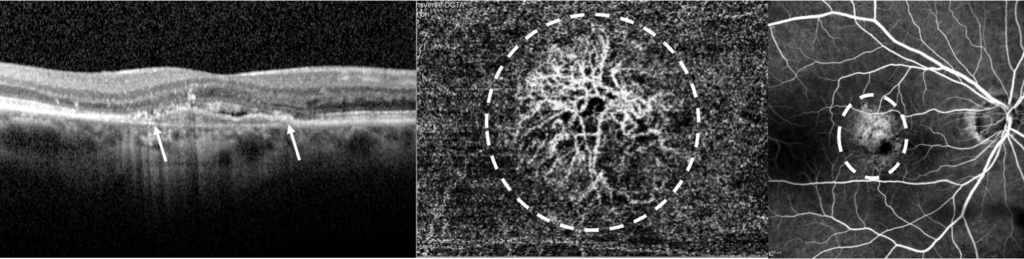

Lors du bilan, l’acuité visuelle est mesurée par l’orthoptiste. Ensuite un OCT maculaire permet de mesurer l’épaisseur de la macula et scanner la rétine à la recherche de signes exsudatifs, inflammatoires, de néovaisseaux… Il est complété par le module OCT Angiographique (OCT-A). Ces mesures servent au diagnostique mais aussi à la surveillance de la DMLA.

Ces premiers examens ne nécessitent pas de dilatation, mais il est courant de réaliser une angiographie à la fluorescéine lors du bilan initial (contre indiquant la conduite après l’examen). Après la dilatation des pupilles, un colorant est injecté dans la veine du bras. Le colorant met en évidence de façon dynamique, la circulation vasculaire maculaire et témoigne de la présence de néovaisseaux.

Coupe OCT maculaire d’un patient atteint de DMLA avec une néovascularisation sous épithéliale (flèche) OCT angiographique révélant la présence d’un néovaisseau (pointillés) Diffusion du colorant en angiographie à la fluorescéine (pointillés).